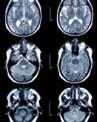

“on the left is an image of a brain, obtained before surgery and viewed midoperation, using our current technology. neurosurgeons rely on images like this during surgery to navigate through the brain, but such technology conveys a relatively limited amount of information and cannot account for changes that occur during the operation. now look at the right: an image of the same patient obtained with more advanced techniques and showing important motor fibers that control movement of the arm and leg. the difference is dramatic but this technique is not accessible at the most critical moment, during the operation, and cannot be updated in real time as the operation proceeds.

“soon the department of neurosurgery will be equipped with advanced technology to see the brain in mid-operation with the same level of detail as we do before and after surgery, and to account for shifts in the position and shape of the brain that occur during surgery. a collaboration with one of the industry’s leading companies and the department of neuroradiology, the technology uses sophisticated gPs-like navigation devices, sliding gantry intraoperative imaging, 3d angiography, and other components that allow neurosurgeons to view— in real time—the results of the procedure. the benefits for patients are immediately clear.

“Mount sinai will be one of the first medical centers in the country to combine this technology with intraoperative biplane cerebral angiography. we already have some of the best neuroimaging specialists in the nation; now we’ll have the intraoperative technology to match that expertise.”